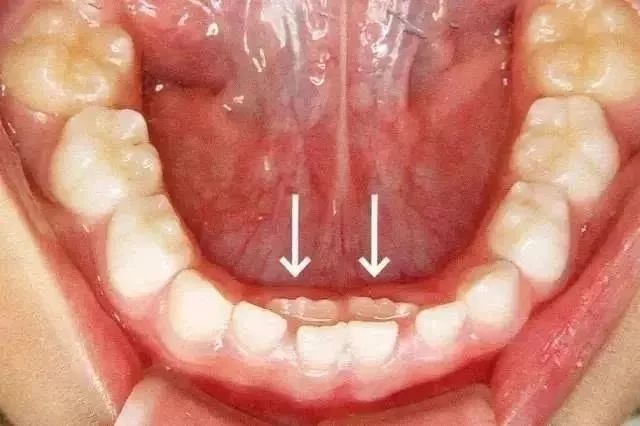

乳牙脱落有一定的时间和顺序,应脱落而不脱落医学上称为乳牙滞留,乳牙滞留往往会导致恒牙不能在正常的位置萌出。有些孩子恒牙已经萌出,乳牙却常常不肯“让位”,迫使恒牙不得不从乳牙的内侧长出,形成“双层牙”现象。

遇到这种情况,应尽快带孩子去医院拔除滞留的乳牙,以利恒牙正常萌出。